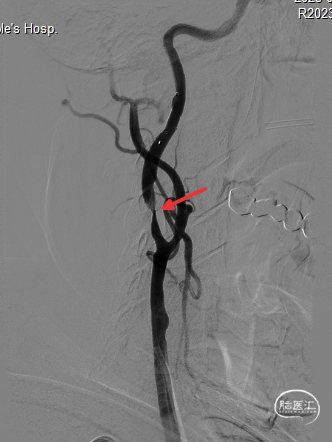

扩张完毕后多角度造影显示狭窄较前明显改善(箭头处)。